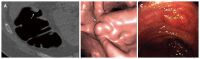

Twenty years after its introduction, computed tomographic colonography (CTC) has reached its maturity, and it can reasonably be considered the best radiological diagnostic test for imaging colorectal cancer (CRC) and polyps. This examination technique is less invasive than colonoscopy (CS), easy to perform, and standardized. Reduced bowel preparation and colonic distention using carbon dioxide favor patient compliance. Widespread implementation of a new image reconstruction algorithm has minimized radiation exposure, and the use of dedicated software with enhanced views has enabled easier image interpretation. Integration in the routine workflow of a computer-aided detection algorithm reduces perceptual errors, particularly for small polyps. Consolidated evidence from the literature shows that the diagnostic performances for the detection of CRC and large polyps in symptomatic and asymptomatic individuals are similar to CS and are largely superior to barium enema, the latter of which should be strongly discouraged. Favorable data regarding CTC performance open the possibility for many different indications, some of which are already supported by evidence-based data: incomplete, failed, or unfeasible CS; symptomatic, elderly, and frail patients; and investigation of diverticular disease. Other indications are still being debated and, thus, are recommended only if CS is unfeasible: the use of CTC in CRC screening and in surveillance after surgery for CRC or polypectomy. In order for CTC to be used appropriately, contraindications such as acute abdominal conditions (diverticulitis or the acute phase of inflammatory bowel diseases) and surveillance in patients with a long-standing history of ulcerative colitis or Crohn's disease and in those with hereditary colonic syndromes should not be overlooked. This will maximize the benefits of the technique and minimize potential sources of frustration or disappointment for both referring clinicians and patients.